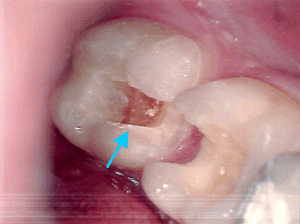

Fäulnis unter neuer Füllung

Foto des Zahnes 35 nach Entfernung einer neuen Füllung

Hier sehen Sie wie es unter einer neuen, weißen Zahnfüllung aussehen kann, die eine Hilfskraft vorZahnröntgen mit Karies einer Woche gemacht hat. Die Patientin kam wegen arger Zahnschmerzen zu uns und im Röntgenbild konnte man unter der Füllung die Karies sehen. Das selbe traf auf einen zweiten Zahn zu. Alle Versuche die Situation zu retten blieben erfolglos und beide Zähne mußten wurzelbehandelt werden, um der Schmerzen Herr zu werden.